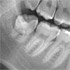

Höchste Bildqualität

X-ERA SMART verfügt über ein einzigartiges Patientenpositionierungssystem im 3D Bereich, das jede Bildverzerrung durch Patientenbewegung komplett ausschließt. Das Technologiekonzept erzeugt eine Bildqualität in extrem hoher Auflösung. Zwei verschiedene Aufnahmegrößen mit einer Voxel Größe von 80μm / 100 μm liefern in jeder Sichtfeldgröße (FoV) exzellente Ergebnisse für die weitere Diagnostik und Behandlung.